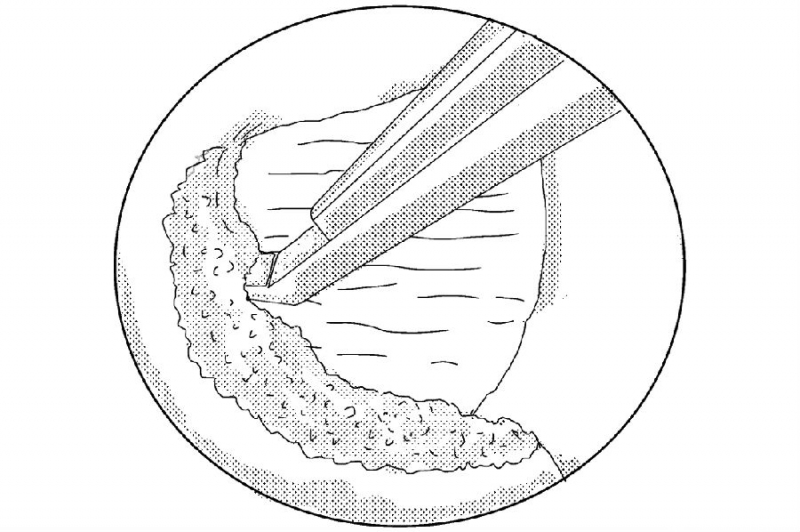

1. 建立通道后的多裂肌三角“地板解剖”;

2. 大刀头清理软组织;

3. 使用4mm金刚砂磨钻将椎板下缘及下关节突内缘磨薄;

4. 使用椎板咬骨钳继续向近端咬除椎板直至黄韧带近端止点;